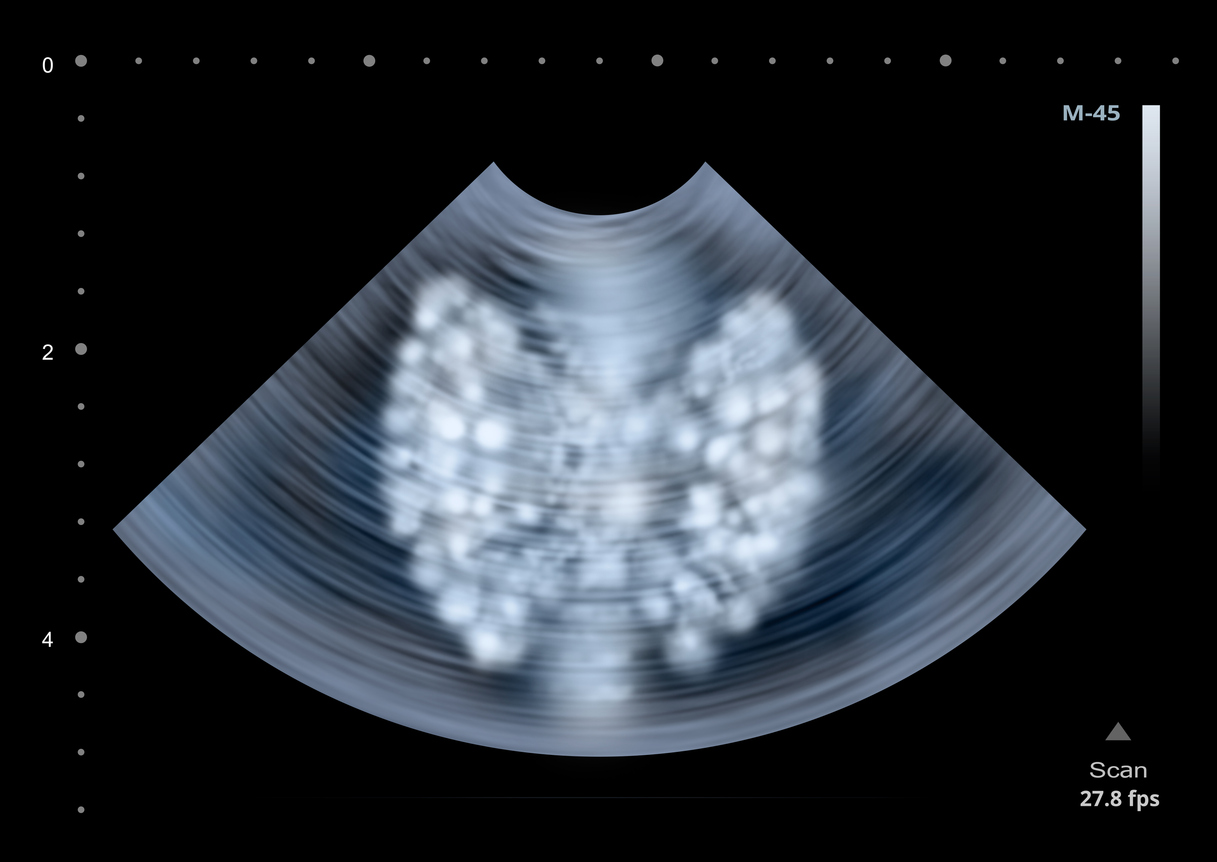

Schwerpunkte liegen in der Behandlung von Schilddrüsenkrebs, einschließlich seltener Schilddrüsenkarzinome (radiojodrefraktäres Karzinom, PDTC und ATC, Medulläres Schilddrüsenkarzinom), von neuroendokrinen Tumoren des Gastrointestinaltrakts, hormonaktiven und inaktiven Hypophysentumoren, Tumoren der Nebenschilddrüsen und der Nebennieren einschließlich Nebennierenkarzinom, malignes Phäochromozytom, Nebenschilddrüsenkarzinom sowie vererbbarer endokriner Tumorerkrankungen (MEN1, MEN2, Carney Complex, Paragangliome, Neurofibromatose u.a.).